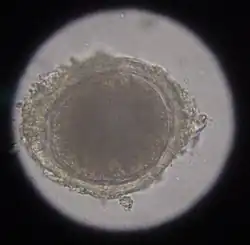

In the case of worms in vomit, the diagnosis can already be made without special examinations. A roundworm infestation can be detected with relative certainty by microscopic detection of the eggs extracted from the feces using the flotation method.

Infection with hookworms often remains asymptomatic in cats. In more severe infestations, they can cause emaciation, anemia or diarrhea. As with roundworms, the infection is detected by detecting the eggs in the feces using a flotation method. They are oval, smaller than roundworm eggs (about 60×40 μm in size) and furrowed stages are already visible inside when the eggs are laid.

Hairworms are most commonly found as parasites in the gastrointestinal tract in cats, for example capillaria putorii. They are considered to cause little disease, but occasionally cause vomiting and diarrhea and, rarely, peptic ulcer disease with anemia.[6] The eggs of gastrointestinal hairworms are oval, about 60-70 × 35-40 μm in size, and can be detected by flotation techniques.[7]

In the same animal, usually only two to ten cat tapeworms are found, and they excrete about four to five limbs daily. These elongated trapezoidal structures may already be visible to the naked eye in the anal region. The coated oncospheres, which are about 35 μm in size, can be detected in the feces using flotation methods. In one study, an infestation rate of 25.9% was determined in autopsies, of which only 10% were detected by flotation and 27% by centrifugation.[10] In addition, the eggs cannot be distinguished morphologically from those of other members of the taeniidae (including the fox tapeworm).